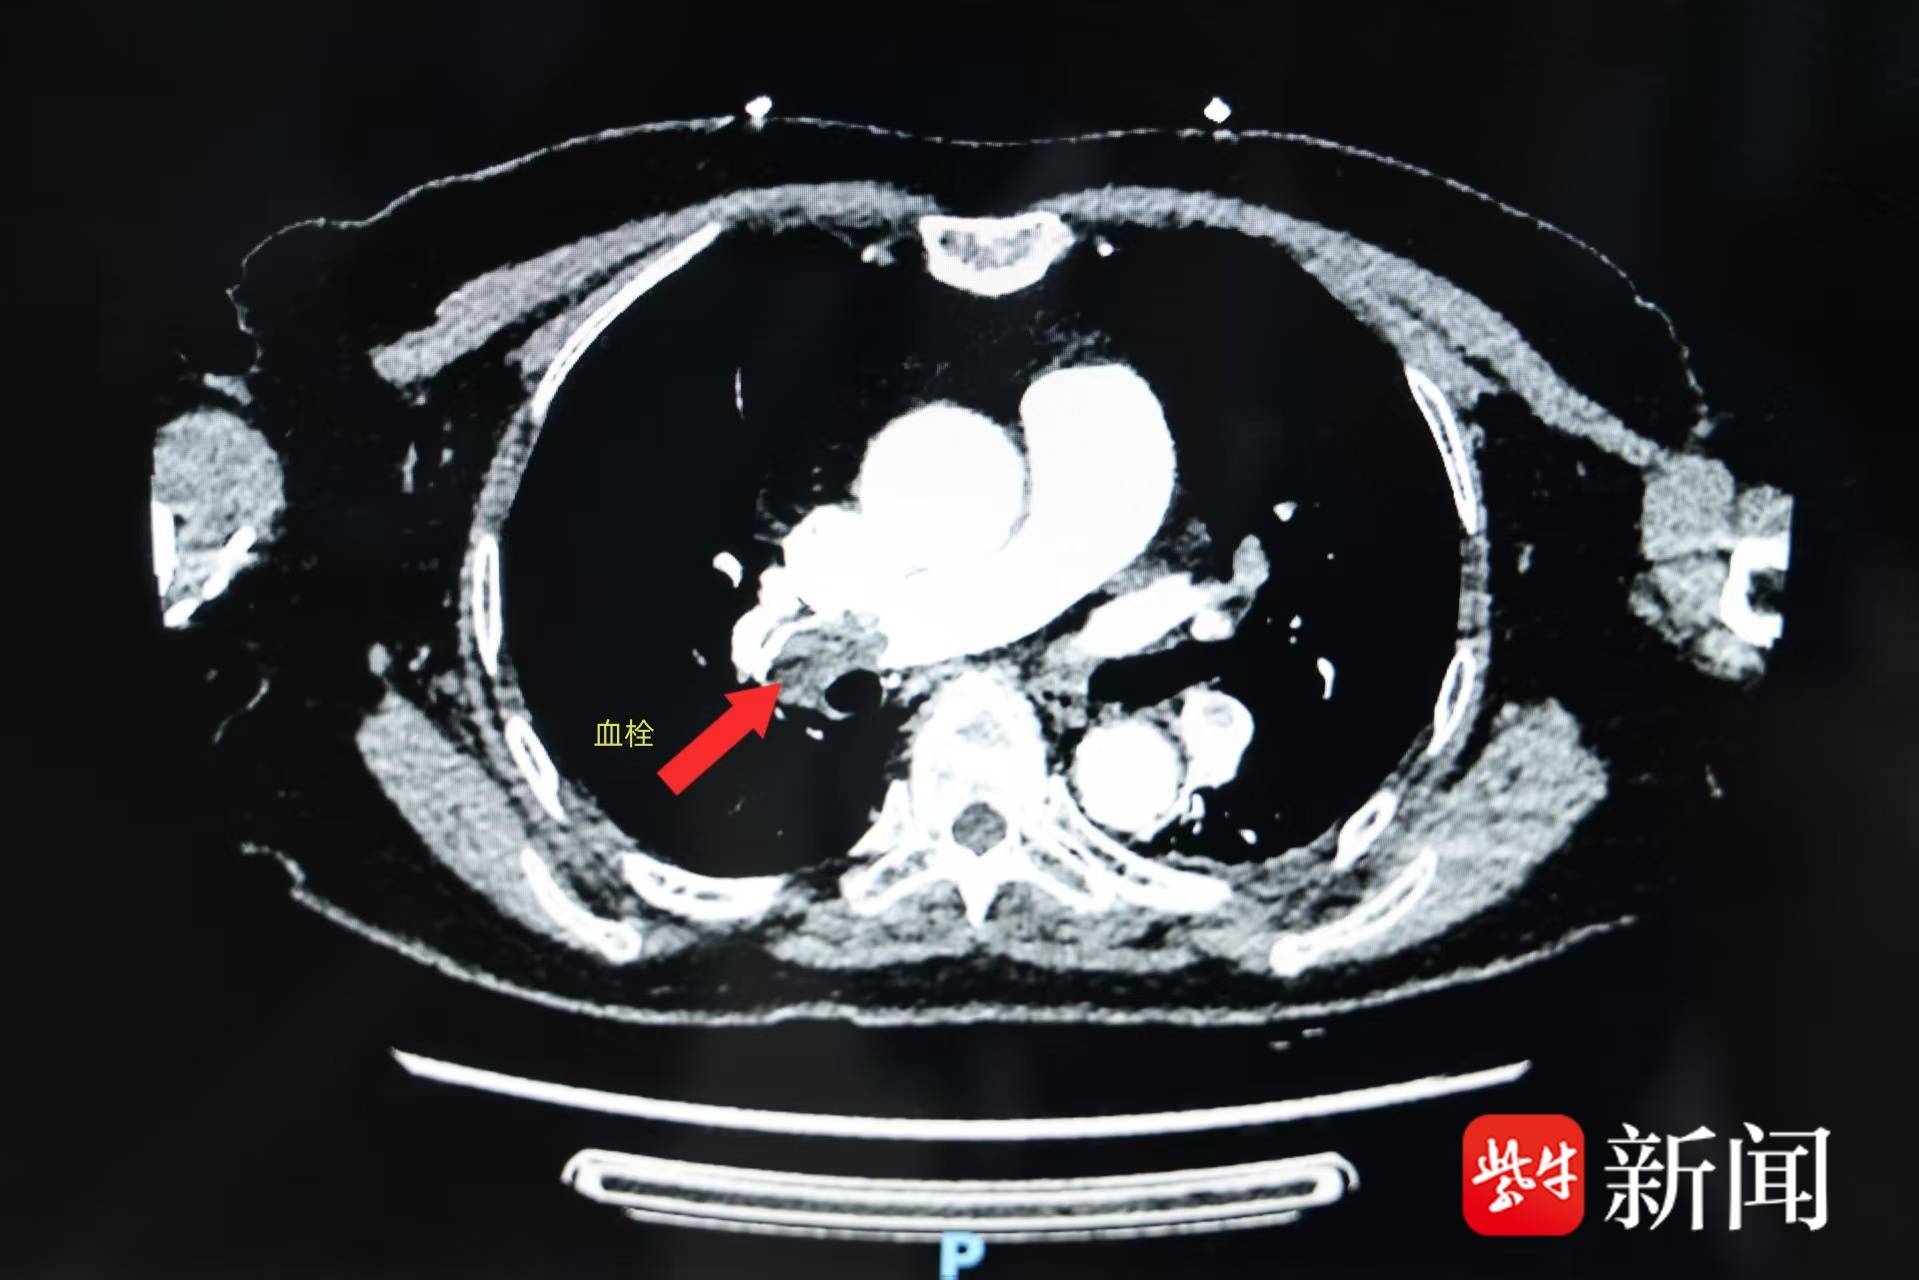

急诊科医生先通过肺部CT排除气胸、重症肺炎,再用心电图和心肌酶排除心梗。当看到血液中“D-二聚体”(血栓重要指标)显著升高,怀疑是急性肺栓塞,随后肺动脉CTA确诊“右下肺动脉栓塞”。好在吴先生就诊及时,血流动力学稳定,医生立即给予抗凝治疗。3个月后复查,他肺部的血栓已完全消失。